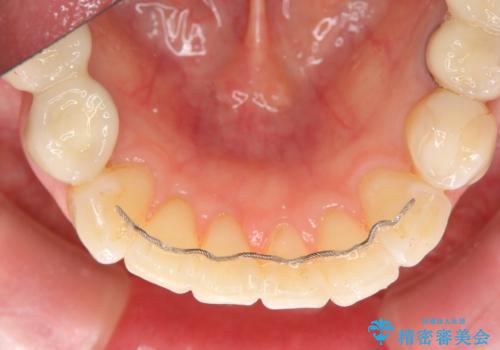

- 矯正装置

- インビザライン

- 下顎前歯のガタつきにより上顎前歯のクラウンに突き上げ・動揺が認められ、また歯ぎしりもあることから下顎前歯のみの小矯正をインビザライン で行うこととなりました。

- マウスピース型矯正装置の長時間装着(1日20時間以上)が必須です